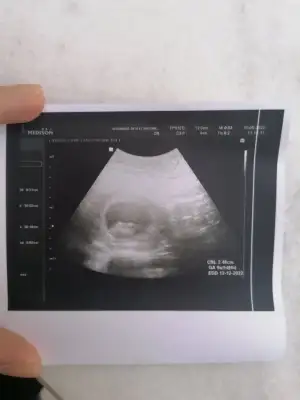

Bu varprenses gibi duruyor 7 haftaşık görüntüsü var mı?

karından ise buda evet prenses gibiBu varPasha22 6.3 haftalık birtane oğlum var 10 yaşında bakalım hayırlısı olsun